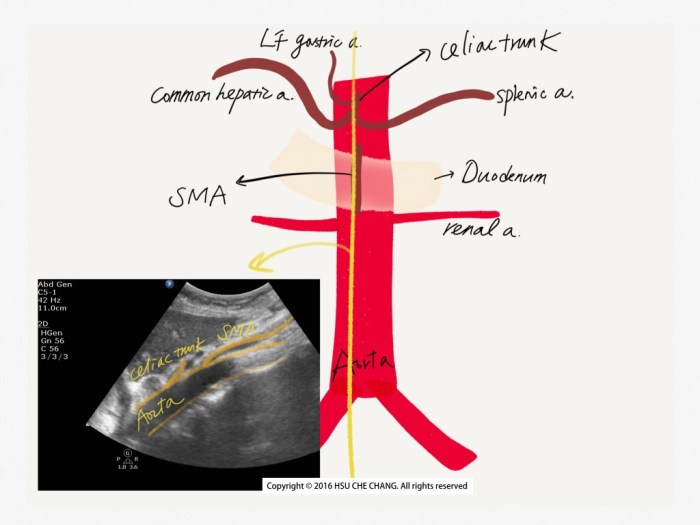

當我們一路從劍突下方往下掃描,第一個中要分支就是celiac trunk。 Celiac trunk 應該分出三條主要血管:common hepatic artery (*註) / splenic artery / left gastric artery。

但是left gastric artery較小,我們一般常看見 common hepatic artery & splenic artery 形成的特殊形態 (我是覺得有點像豆芽啦…):

3. SMA (Superior mesenteric artery)

SMA 從Aorta 分出,就剛好在celiac trunk 之下,所以在掃瞄時一過celiac trunk 就會看見SMA冒出來,而且SMA 跟Aorta 中間還夾了十二指腸 duodenum跟左腎靜脈 left renal vein:

但SMA 在transvere scan並無特殊結構可辨認,所以需要動態確認,或是轉成longitudinal view: